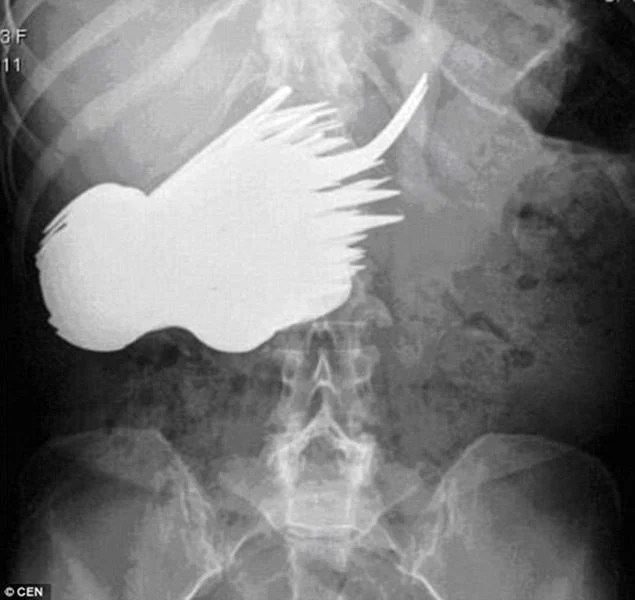

Tweet this video! - - While normally x-rays reveal things like broken bones or fluid filled lungs, every once in a while they expose something a little more strange. How strange? Painfully strange. Get ready to cringe because on this list you'll find everything from knives and wedding rings to cellphones and hand grenades. These are the stories behind the 25 strangest things found in an x-ray. - - - Check out the text version too! - - Here's a preview: Nail through skull Swallowed wedding ring Knife in head Nail gun murder Surgical scissors in abdomen Arrow through skull Swallowed scissors Electric Blanket in Burmese Python Knife through forehead Blade in a puppy's stomach Light bulb in colon Cell phone in colon Drill through head Swallowed cobblestones Keys through eyesocket Tap handle through eye Largest kidney stone ever Swallowed bed springs and batteries Bullet in colon Fork in stomach Magnets in colon Nail through forehead Grenade in head Grenade in stomach Chair leg through head